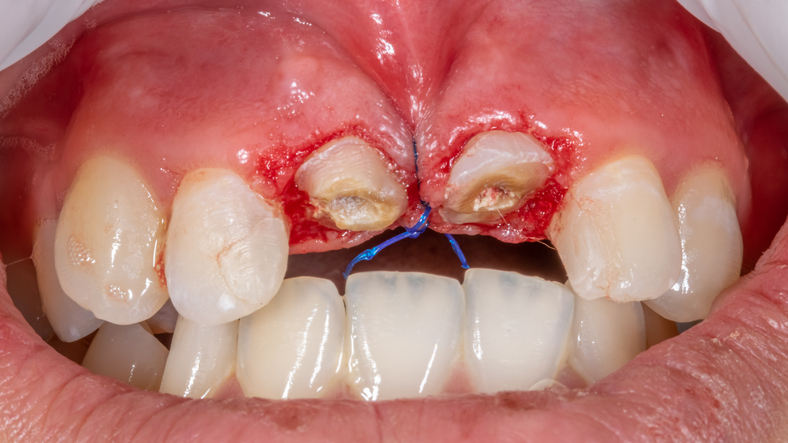

3. 피판술: 잇몸을 절개해 젖힌 후 절제 및 조정 → 정확도 ↑

2. 잇몸 절개 및 치조골 확인

3. 잇몸 또는 뼈 일부 제거

4. 잇몸을 재위치시켜 봉합